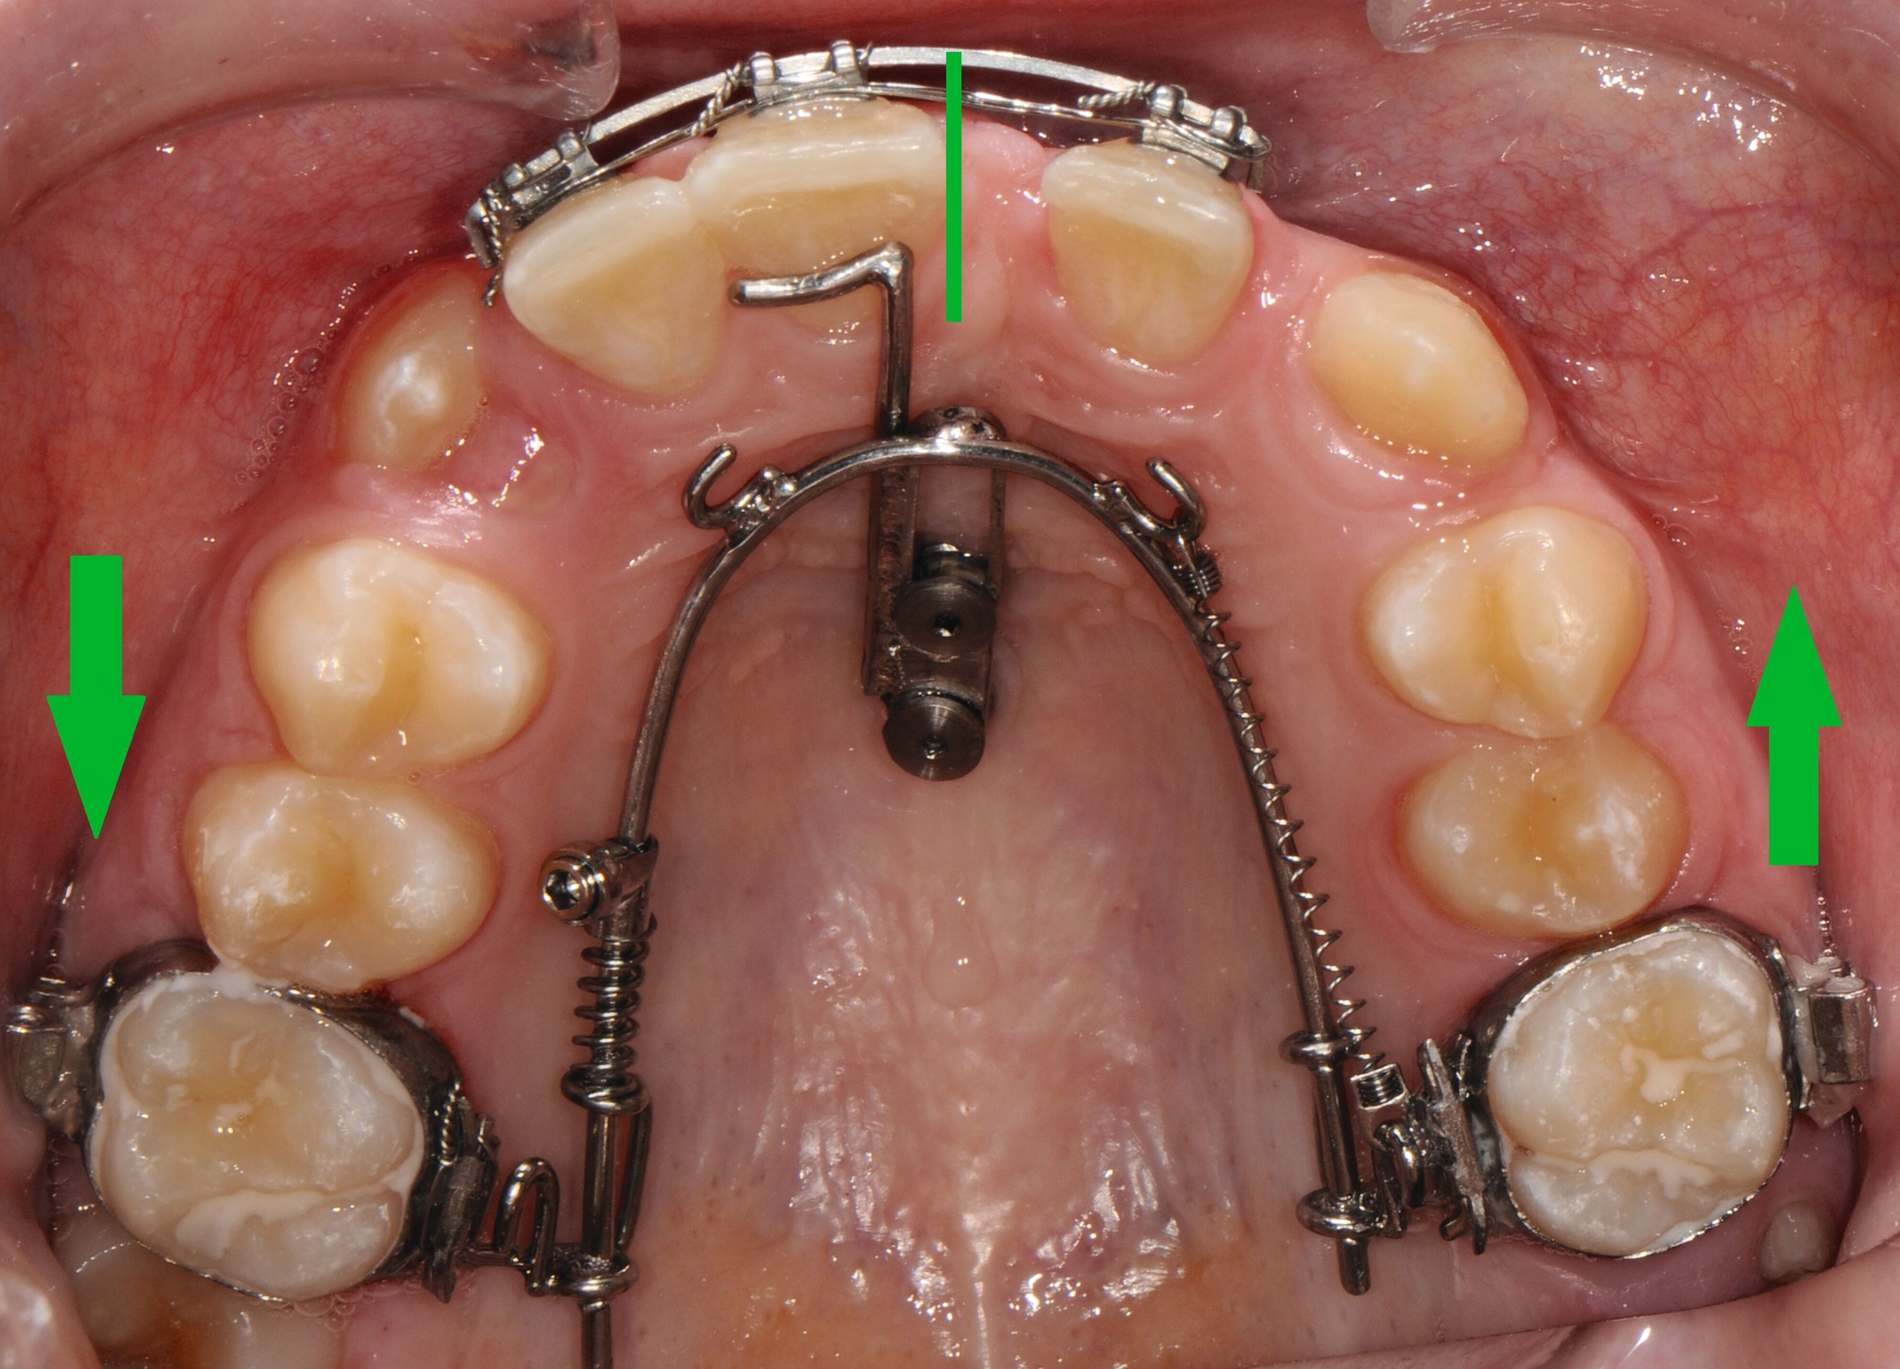

Beispielsweise kann durch eine kieferorthopädische Mesialisation nicht traumatisierter Nachbarzähne auch im wachsenden Kiefer ein traumatisch bedingtes Knochendefizit günstig beeinflusst werden [Pontoriero et al., 1987; Prapas et al., 2008; Stenvik und Zachrisson, 1993] (Abbildung 4).

Durch den Einsatz skelettaler Verankerungshilfen ist es möglich, auch in komplexeren Situationen einen kieferorthopädischen Lückenschluss durchzuführen. Mit digitalen CAD/CAM-Herstellungsmethoden wie dem selektiven Laser-Melting-Verfahren können hochindividualisierte Apparaturen angefertigt werden, die verschiedene Behandlungsaufgaben gleichzeitig adressieren beziehungsweise mit deren Hilfe Kraftvektoren präzise geplant und appliziert werden können.

Zu den weiteren Vorteilen gehören die geringeren Nebenwirkungen auf die Nachbarzähne, die bessere Planbarkeit bei Set-up-basierten Apparaturen, die gute Pflegbarkeit, die einfache Handhabung, die Verkürzung der gesamten Behandlungszeit durch reduzierte Multibracket-Phasen sowie die geringere Beeinträchtigung der orofazialen Ästhetik (Abbildung 5).